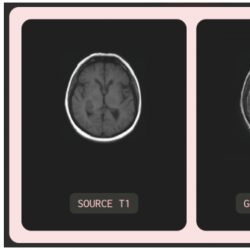

5 Demonstration

A website has been developed as a platform to showcase the conducted experiments. This website serves as a repository of the research findings and provides a convenient means for accessing the experimental data, results, and related materials. The repository can be accessed via

https://github.com/hanahh080601/Generate-MRI-FastAP. As illustrated in Fig.

21, the website offers a user-friendly interface, allowing visitors to navigate through the MRI Synthesis experiments, explore the data, and gain insights into the research process. It serves as a valuable resource for researchers, practitioners, and interested individuals to access and review the experimental work conducted in this study.

Fig. 21

Illustration of the user interface for the demo website.

Specifically, users can select the input contrast and output contrast they desire for image synthesis upon accessing the website. They can then choose to upload files from their local device (the uploaded image must match the selected input contrast). Alternatively, users may only select the input and output contrast, after which the system will generate image using input data from the BraTS2020 and IXI datasets. This feature is used to qualitatively assess the quality of the generated images compared to the original ones.

Based on observation in Fig.

21, T1 is selected as the input contrast, T2 as the output contrast, and the IXI dataset is the chosen dataset. The system automatically chose a random T1 image from the test set of the IXI dataset and sent a request for the model to generate the T2 image. Additionally, the system also selected the ground truth T2 image from the dataset and displayed both for user comparison.